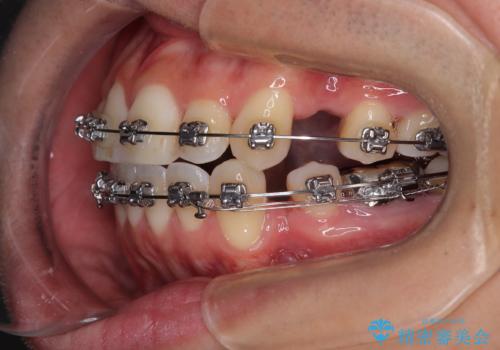

- 矯正装置

- メタルブラケット

- 口元の突出感が強く、口が閉じにくいことを主訴として来院された患者さんの症例をご紹介します。

前歯部の叢生(デコボコ)も認められ、歯がきれいに並ぶためのスペースが不足している状態でした。

これらの問題を総合的に改善するため、上下左右の第一小臼歯を計4本抜歯し、スペースを確保する治療計画を立てました。

抜歯したスペースを活用して前歯を後ろへ下げることで、口元の突出感を大きく改善。

奥歯の噛み合わせがずれている「シザーズバイト」を適正に整えることで、見た目だけでなく機能性も向上し、安定した咬合が獲得できました。